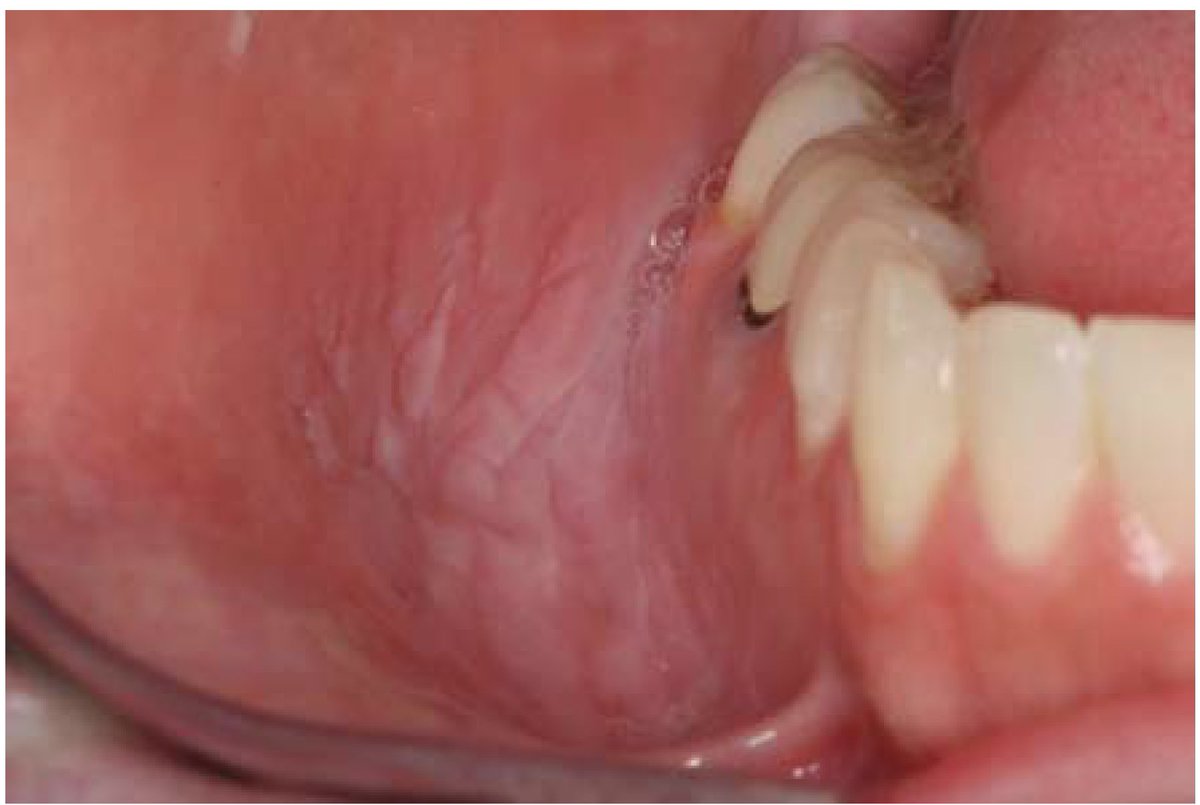

الجروح اللي تتكون بسبب وجود سن حاد/حشوة مكسور/تقويم الاسنان وتتكون غالباً على:

جانبي اللسان

الجزء الداخلي من الشفايف

جزء من الخد القريب من الأسنان

معالجة هالجروح يكون بتنعيم الجزء الحاد من السن/الحشوة ووضع شمع على التقويم. غالباً تختفي بعد اسبوعين من معالجة السبب